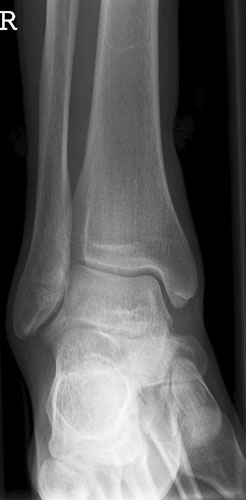

OSG seitlich

Fehler

Doppelkonturierung im vorderen Teil der Talusrolle. Die Fibula ist gegen dem Malleolus internus nach ventral verschoben. Die Längsachse des Talus ist verkürzt. Das untere Sprunggelenk kann nicht beurteilt werden.

Abhilfe

Keilkissen unter den Calcaneus legen bzw. Fuß flacher auf den Zehen auflegen lassen.